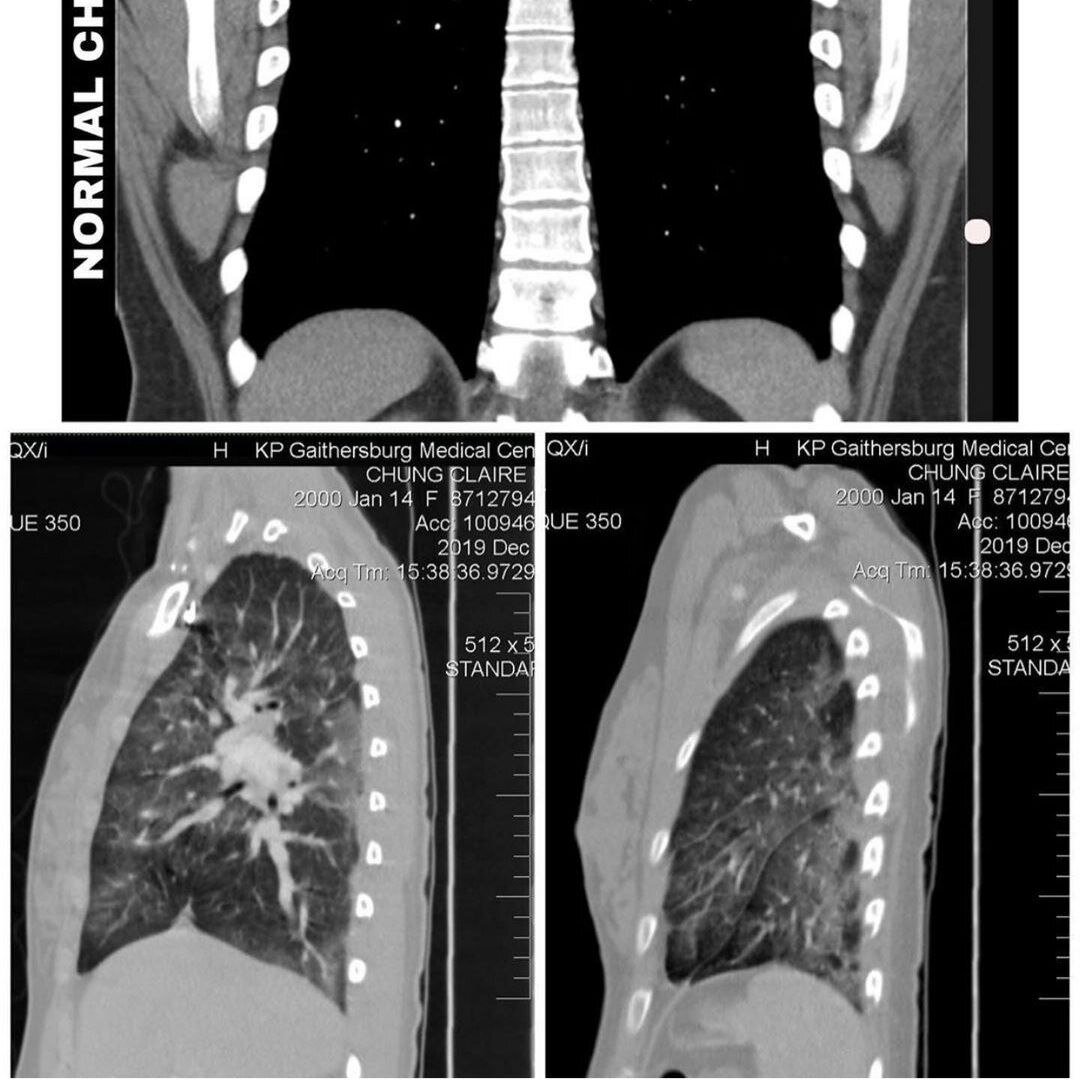

Прочитал историю 19-ти летней девушки Claire и скажу честно у меня волосы зашевелились в самых интересных местах! . Суть такова (полную историю можете почитать у неё в профиле @clairechunggg), что как и большинство подростков она во всю курила вейп (электронная сигарета), полагая, что это просто клевая модная штука Перед Рождеством у неё в течении 3 недель у неё держалась температура под 40 без каких-либо симптомов, предполагая, что это грипп она принимала безрецептурные препараты, но толку от них не было. Рентгенография грудной клетки показала, что у неё была легкая пневмония в нижней части левого легкого. Приём антибиотиков ни помог, поэтому она была доставлена в отделение реанимации . Здоровые легкие при сканировании должны быть черными. Её 19-летние легкие были полностью мутными и белыми на снимках. Врачи не могли определить, показывало ли при сканировании жидкость, кровь, бактерии, инфекции и т. д. Как следствие они не могли фактически понять, от чего нужно лечить Claire . После

Здоровые легкие при сканировании должны быть черными. Её 19-летние легкие были полностью мутными и белыми на снимках. Врачи не могли определить, показывало ли при сканировании жидкость, кровь, бактерии, инфекции и т. д. Как следствие они не могли фактически понять, от чего нужно лечить Claire

Бронхи ЧРЕЗВЫЧАЙНО воспалены, и вся белая мутность (которая должна быть черной и чистой при здоровом сканировании) - это поврежденная ткань. Никаких исследований по влиянию электронных сигарет нет, поэтому врачи и не думают на них зачастую, полая что это просто очередная забава